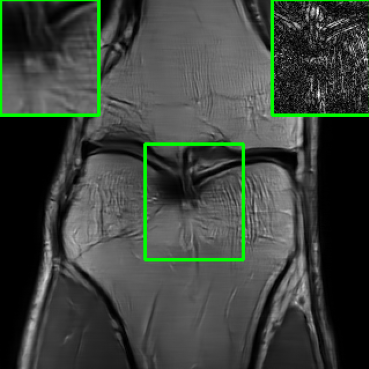

In addition to additive perturbations, the study presented in [32] underscores an additional potential source of instability that MoDL may face during testing. This source stems from changes in the measurement sampling rate, leading to perturbations in the sparsity of the sampling mask within [10]. Furthermore, in this paper, we consider another variation that MoDL could encounter during the testing phase, involving a shift in the k-space sampling locations within the matrix , resulting in the construction of a nonidentical forward operator for testing. For this case, , where . Figure 1 illustrates reconstructed images from the instabilities considered in this paper.

| PSNR = 29.8 dB | PSNR = 22.01 dB | PSNR = 20.28 dB | PSNR = 23.14 dB |

| (a) | (b) | (c) | (d) |

5.4 Visualizations

We now present visual samples from both the knee and brain datasets. Specifically, Figure 5 presents visual comparison of image reconstructions and their associated reconstruction errors within a closely examined region. Each image in the figure includes two inset panels in the top-left and top-right corners. The top-left inset panel, enclosed within a green bounding box, serves as a reference for the region of interest in the image. In contrast, the top-right inset panel depicts an error map in relation to the ground truth. Notably, our method stands out in its ability to capture the original image’s features, surpassing the performance of alternative methods (as also evident from the reported PSNR values). This visual comparison underscores the superior quality and accuracy of our approach in the robustification of the MRI image reconstruction task.